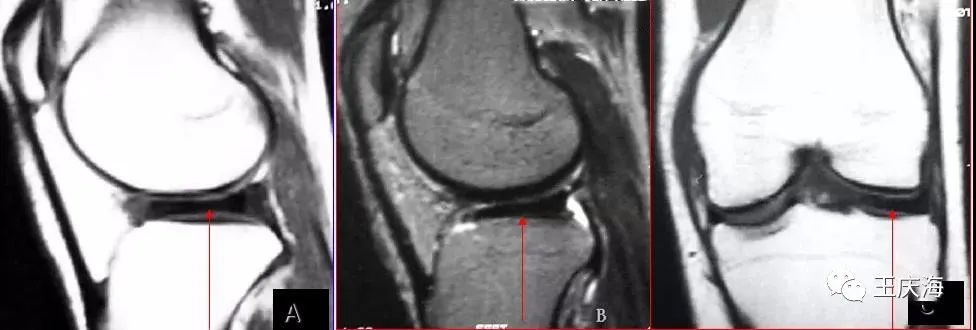

厚板型盘状半月板,矢状面T1WI(图A)和T2WI(图B)显示半月板前后角连续。冠状面(图C)见半月板体部的横向宽度明显增大,等同于外侧胫骨关节面的横径,半月板游离缘厚度基本与囊缘一致。

楔型盘状半月板,冠状面T1WI测量半月板体部的横向宽度超过外侧胫骨平台关节面宽度一半以上,半月板游离缘的厚度明显小于囊缘。